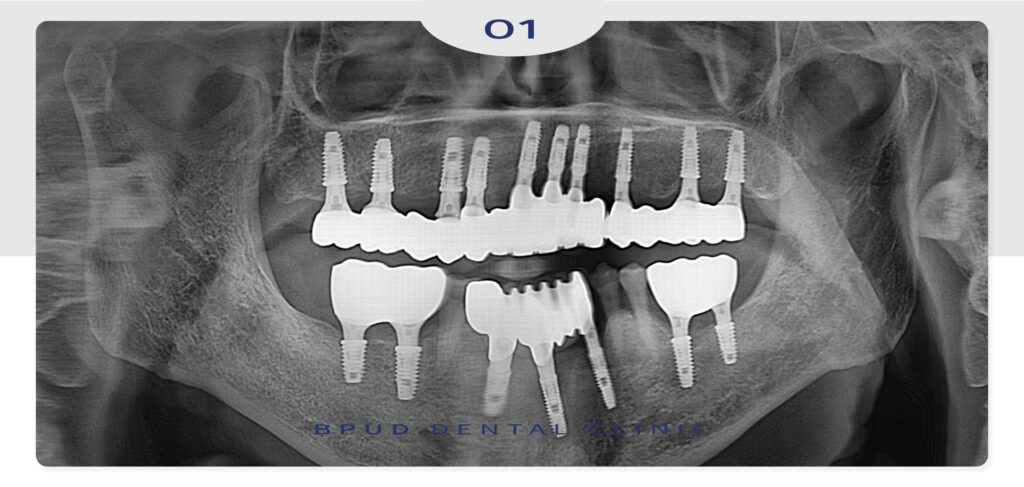

25.09.20

위, 아래 모든 임플란트를 마무리한 후의

모습입니다.

예전 사진과 비교해도 심미적으로 바뀌고

양쪽으로 식사도 잘할 수 있으시다며

환자분께서도 매우 만족하셨습니다!

24.03.30